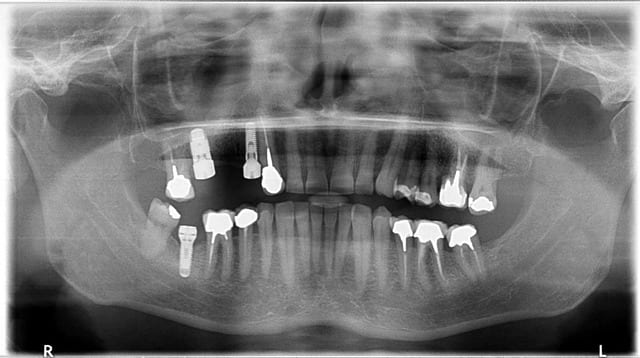

en haut: TSV zimmer amha un 3,7mm et un 6mm

en bas du zimmer mais un Advent (tissue level), 3,7mm mais plateforme 4,7mm...attention pour l'Advent, les pièces prothétiques sont spécifiques car l'hex est de 3mm au lieu de 2,5mm pour les TSV sur la plateforme 4,7mm...;-)